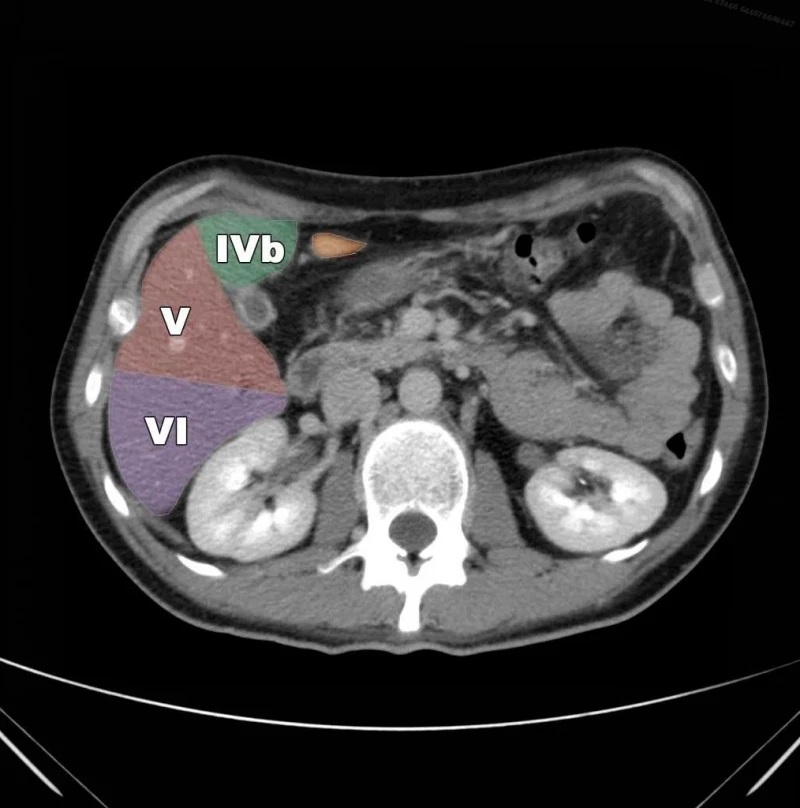

Сегментарное строение печени — важная часть ультразвукового исследования, поскольку информация о том, в каком сегменте органа располагается поражение имеет большое значение. Печень может быть разделена печеночными венами следующим образом: правая вена делит правую долю на два сегмента — задний и передний (рис. 10) и левая вена разделяет левую долю на латеральный и медиальный сегменты (рис. 11). Теперь, если мы проведем продольные плоскости через левую, среднюю и правую главные воротные вены (рис. 12), то печень будет разделена на восемь сегментов (рис. 13).

Рис. 13. Печень разделена на восемь сегментов следующим образом: 1 — хвостатая доля, которая ограничена сзади нижней полой веной и спереди главной печеночной бороздой; 2 и 3 — левый латеральный сегмент; 4 — левый медиальный сегмент; 5 и 8 — правый передний сегмент; 6 и 7 — правый задний сегмент.

По классификации Куино и в правой, и в левой доле печени расположено по 4 сегмента. Воротная вена делит доли печени на верхние и нижние, передние и задние сегменты.

На диафрагмальной поверхности сегменты нумеруются по часовой стрелке, а на висцеральной против часовой стрелке; на изображениях обычно римскими цифрами. В медицинской терминологии крайние области принято называть латеральными, срединные—медиальными.

4

4-ый сегмент печени. Левый медиальный. Бисмут (Н. Bismuth) в 1982 предложил делить сегмент IV на IVa и IVb: левый медиальный верхний и нижний.